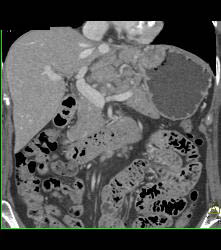

Gastric Adenocarcinoma With Nodes